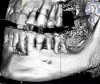

Fig 1. Presurgical panoramic radiograph of a patient with severe periodontal disease and who is an All-on-4–style treatment candidate.

Figure 1